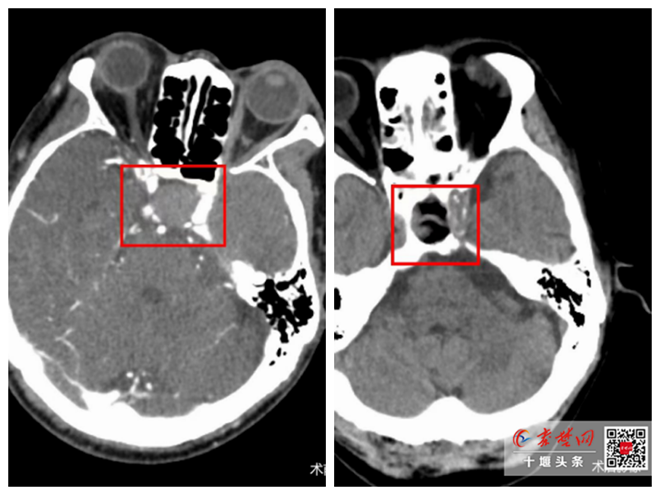

秦楚网-十堰头条讯 文、图/记者 秦洪涛  特约记者 马婷婷 报道:近日,十堰市人民医院神经外科一病区戴永建主任团队成功完成一例神经内镜下经鼻蝶垂体瘤切除手术,运用一根直径仅有几毫米的内窥镜,经由鼻腔,直达病变部位,通过小切…

肺部血管畸形引发脑梗塞 十堰人医介入科成功开展肺动静脉瘘介入治疗

秦楚网-十堰头条讯 文、图/记者 秦洪涛 特约记者 马婷婷 彭晓丽 通讯员 张正宇 报道:近日,十堰市人民医院介入科、神经内科、重症医学科成功联合诊治了一例因肺动静脉瘘引发的反常脑梗塞患者,赢得患者及家属赞誉。该疑难病例的成…

十堰广电讯(通讯员 马婷婷 张正宇)日前,十堰市人民医院介入科、神经内科、重症医学科成功联合诊治了一例因肺动静脉瘘引发的反常脑梗塞患者,赢得患者及家属赞誉,该疑难病例的成功救治体现了十堰人医作为秦巴山核心医院高水平的综合…